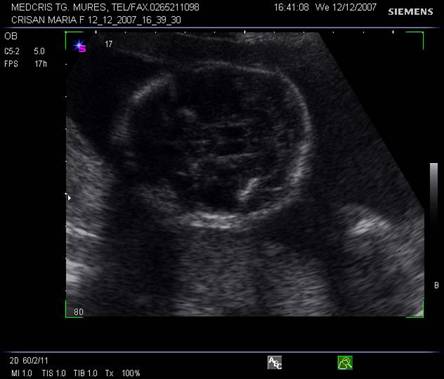

Planul VI trece prin baza craniului si defineste fosele anterioara, mijlocie si posterioara. Osul sfenoidal hiperecogen apare la jonctiunea foselor anterioara cu posterioara. Portiunea joasa a cerebelului si puntea sunt vizibile.

Fig. nr. 154. Planul VI de sectiune frontala craniana.